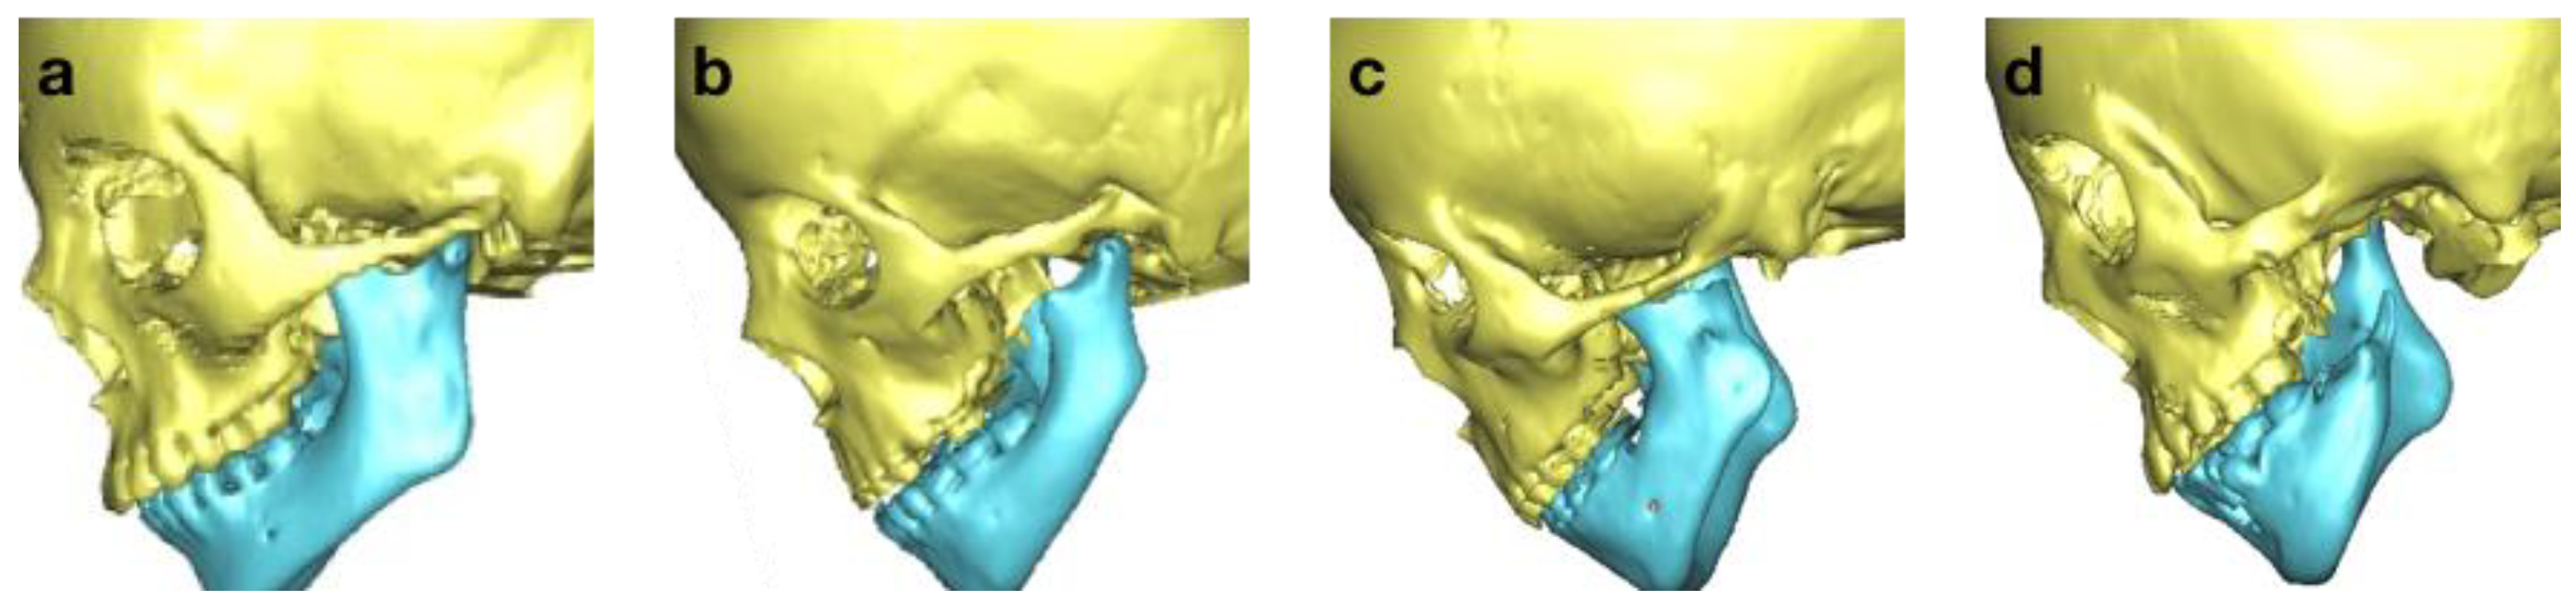

| M (Mandible) | |

| M0 | normal mandible |

| M1 | small mandible and glenoid fossa with short ramus |

| M2a | abnormally shaped and short ramus (glenoid fossa in acceptable position) |

| M2b | abnormally shaped and short ramus (glenoid fossa is inferiorly, medially, and anteriorly displaced with severe hypoplasia of condyle) |

| M3 | absence of ramus and glenoid fossa |